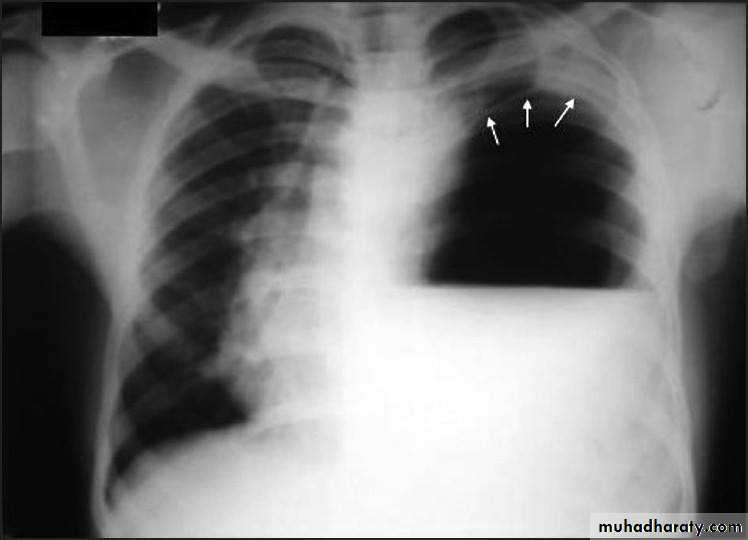

Pulmonary hydatid cyst